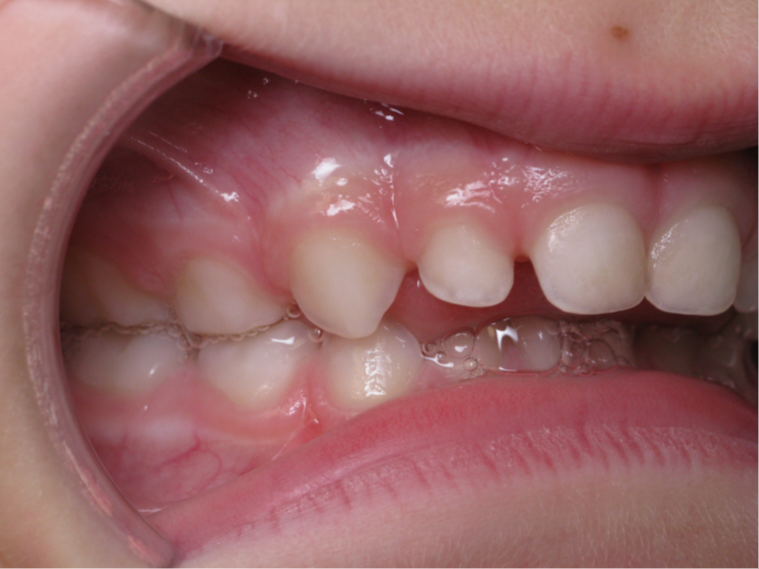

6 décalage sagittal 5 ans

Décalage entre les dents d avant en arrière